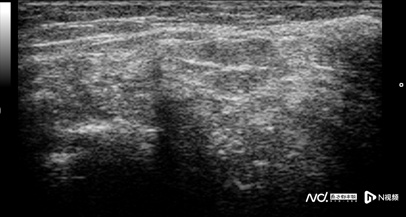

来到了广医二院后,医生为小源进行了床旁关节超声评估,对影响活动最严重的膝关节进行了微创针刀镜灌洗治疗术,冲洗出大量石灰渣样物质,加强降尿酸,并联合护理团队加强伤口清创护理,分阶段精准护理,促进伤口愈合修复。小源的病情迅速得到控制,全身疼痛明显缓解。